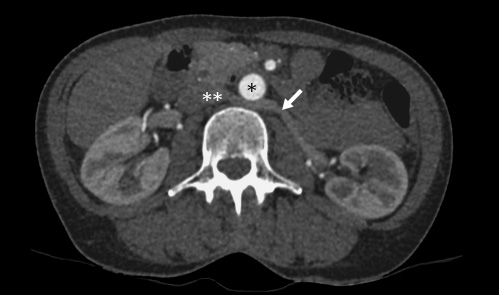

From 221 patients who underwent laparoscopic donor nephrectomy between 2011 and 2017, 11 (4.98%) showed the feature of a retroaortic left renal vein (Fig. 1). In 8 patients (72.7%) decision for left kidney donor nephrectomy was made.

CT scan of a retroaortic left renal vein. *, aorta; **, vena cava; →, retroaortic left renal vein.